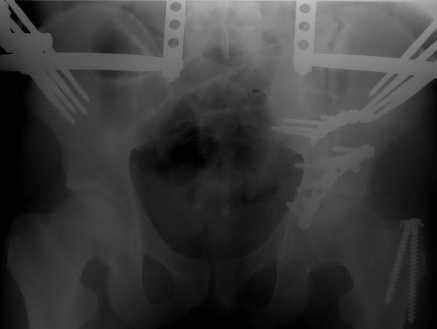

Оценив свои возможности и совместив с вашими рекомендациями и советами (большое спасибо Рункову!), пошли задне-наружным доступом, с отсечением большого вертела. Закрепились 2-мя пластинками. Сверху закрепили аппаратом( передней рамой). На область перелома самого гребня повздошной кости не вмешивались. Снимки высылаю. Жду ваших отзывов и комментариев.